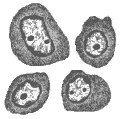

Согласно Международной гистологической и цитологической классификации опухолевых заболеваний кроветворной и лимфоидной тканей, в основу которой положен клеточный состав новообразований и характер распространения, опухоли системы крови, или гемобластозы, делят на две группы: лейкозы (лейкемии) – системные опухолевые заболевания кроветворной ткани; лимфомы – регионарные опухолевые заболевания кроветворной и/или лимфоидной ткани. Такое деление является в значительной степени условным, поскольку ограниченный опухолевый рост и диффузная опухолевая инфильтрация могут иметь место одновременно или последовательно у одного больного. Актуальность проблемы Лейкемии и лимфомы, включая лимфому Ходжкина, составляют приблизительно 8% от всех злокачественных новообразований и все вместе входят в число 6 самых частых видов злокачественных опухолей. В США каждый год лейкемиями заболевает около 25000 человек, из них умирает 15000-20000. Уровень смертности в последнем десятилетии резко снизился в результате повышения эффективности терапии. Острые лейкемии составляют около 50-60% от всех лейкемий, причем острая миелобластная лейкемия встречается несколько чаще, чем острая лимфобластная лейкемия. Хронические лейкемии составляют около 40-50% от всех лейкемий, причем хроническая лимфоцитарная лейкемия встречается несколько чаще, чем хроническая миелоцитарная лейкемия (рис. 1). Рис. 1. Заболеваемость различными видами лейкемий в зависимости от возраста ОЛЛ – острая лимфобластная лейкемия; ХЛЛ – хроническая лимфоцитарная лейкемия; ОМЛ – острая миелобластная лейкемия; ХМЛ – хроническая миелоцитарная лейкемия. В последние годы получила распространение в большинстве стран классификация франко-американо-британской группы гематологов (FAB-система, табл. 1). Согласно этой классификации выделяют три варианта острого лимфобластного лейкоза (L1, L2, L3) в зависимости от размеров бластов, структуры ядра и цитоплазмы, а также по иммунологическим (иммуноморфологическим) или генетическим признакам (см. табл. 2, 5). Острая миелобластная лейкемия также классифицируется по FAB-системе в зависимости от “зрелости” и направленности дифференцировки лейкозных клеток. Она включает типы М1, М2, М3, М4, а также моноцитарную лейкемию (М5), эритролейкемию (М6) и мегакариоцитарную лейкемию (М7), которые обычно рассматривают отдельно. Таблица 1 Франко-американо-британская классификация острых лейкемий Острая лимфобластная лейкемия (ОЛЛ) L1 «Гомогенные» лимфобласты среднего размера; иммунологически немаркируемые, но охватывающие несколько типов, включая простую ОЛЛ и пре-В ОЛЛ; встречается у детей; имеет самый хороший прогноз. L2 Гетерогенные бластные клетки; также смешанная группа, некоторые немаркируемые, Т-клеточные; наблюдается обычно у взрослых и имеет плохой прогноз. L3 Гомогенные базофильные бластные клетки (типа клеток при лимфоме Беркитта), состоит из В-клеток и имеет плохой прогноз. Острая миелобластная лейкемия (ОМЛ) M1 Состоит только из миелобластов без созревания M2 Миелобласты с признаками созревания M3 Острая промиелобластная лейкемия; промиелобласты имеют множество темных азурофильных цитоплазматических гранул. M4 Острая миеломонобластная лейкемия, развивающаяся из общих клеток-предшественников моноцитов и гранулоцитов. M5 Острая монобластная лейкемия M6 Эритролейкемия (синдром Ди Гуглиельмо; доминируют эритробласты при присутствии миелобластов. M7 Мегакариобластная лейкемия Монобластная лейкемия подразделяется на два типа лейкемий: острую монобластную (тип Шиллинга) и острую миеломонобластную (тип Нигели). Не существует хронических форм лейкемий данного типа. Острая моноцитарная (монобластная) лейкемия характеризуется пролиферацией монобластов. Они могут быть отдифференцированы от других бластов только при использовании цитохимических маркеров (табл. 2). Острая миеломоноцитарная лейкемия характеризуется наличием бластов, которые имеют признаки миелобластов и монобластов как морфологически, так и цитохимически. Таблица 2 Цитохимическая идентификация острых лейкемий